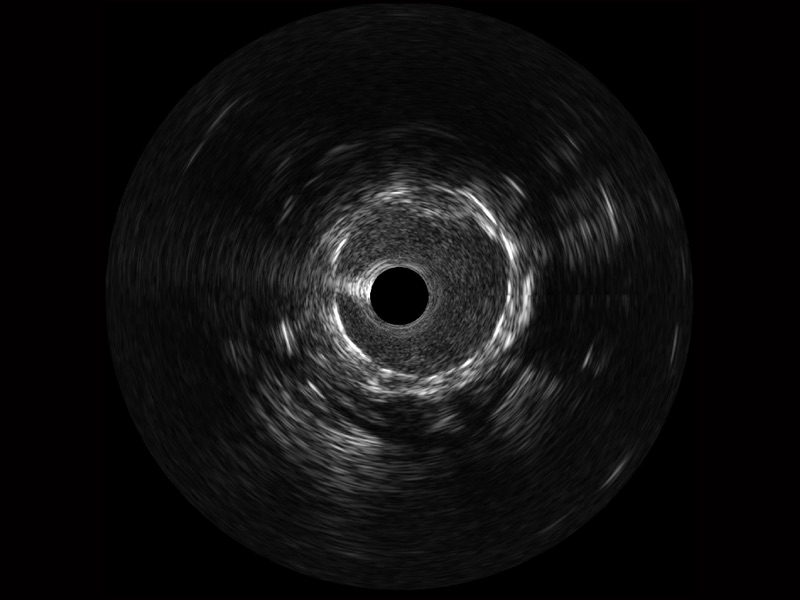

• 传统IVUS图像

对比传统IVUS导管成像,诸侯快讯官网宽频IVUS图像的近场支架梁显影更细腻,远场中膜外血管仍清晰可辨,兼顾远中近,兼顾分辨力与穿透深度